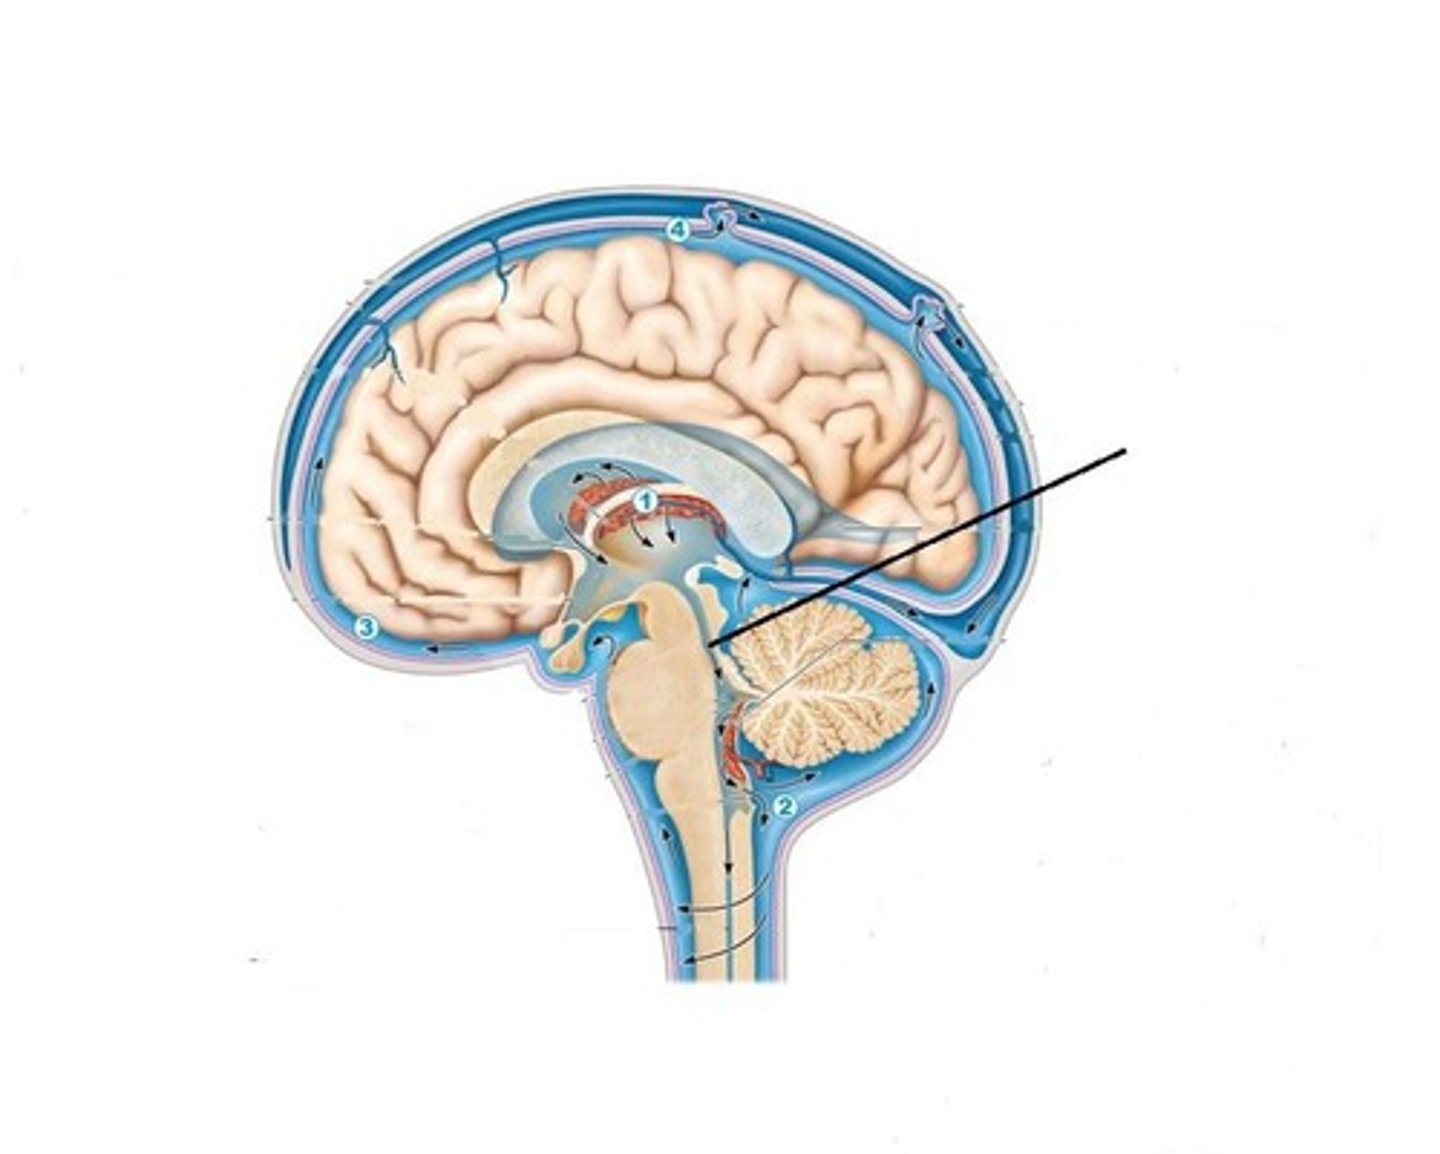

Cerebral Aquaduct

A fluid-filled canal that runs through the midbrain connecting the third and fourth ventricles.

Fourth Ventricle

One of the components of the ventricular system in the brain, along with the lateral and third ventricles. It extends from the cerebral aqueduct (of Sylvius) to the obex and is filled with CSF.

Choroid Plexus

A highly vascular portion of the lining of the ventricles that secretes cerebrospinal fluid.